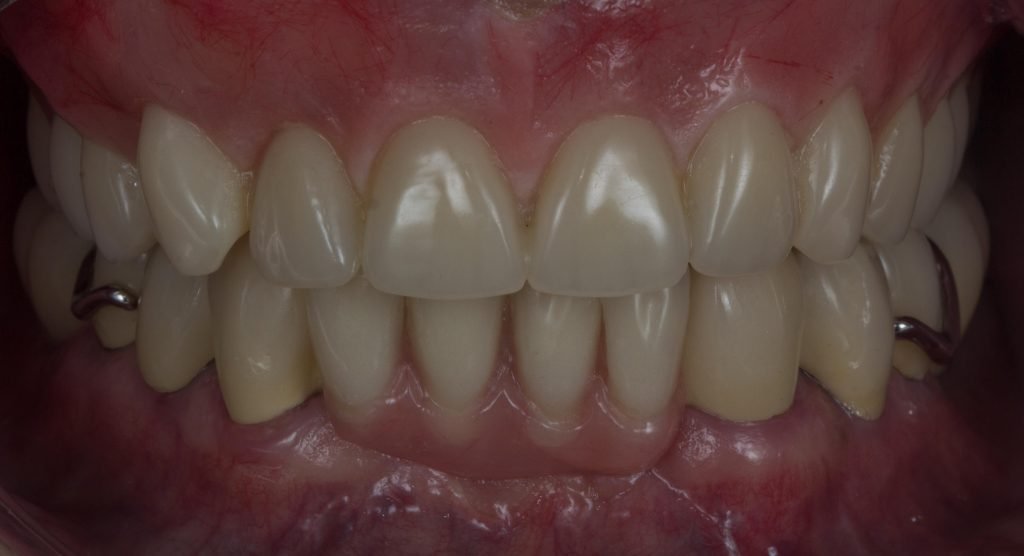

Punto Bajío Casos Clínicos Prótesis Fija sobre Implante unitario Inicio Provisional Final Prótesis Parcial Fija sobre 2 Implantes 2 Implantes Final Prótesis Bucal Removible Inicial Inicial Superior Inicial Inferior Rayos X Inicial Rayos X Inicial Frontal Final Final Superior Final Inferior Prótesis Parcial Fija/ Coronas de Circonio Sonrisa Inicial Foto Inicial Foto Inicial Inferior Foto Final Inferior Foto Final Sonrisa Final Prótesis Total Protesis Inmediatas 1 Protesis Inmediatas 2 Prótesis Removible/ Coronas Metal-Ceramica Carillas Incrustaciones Endodoncia